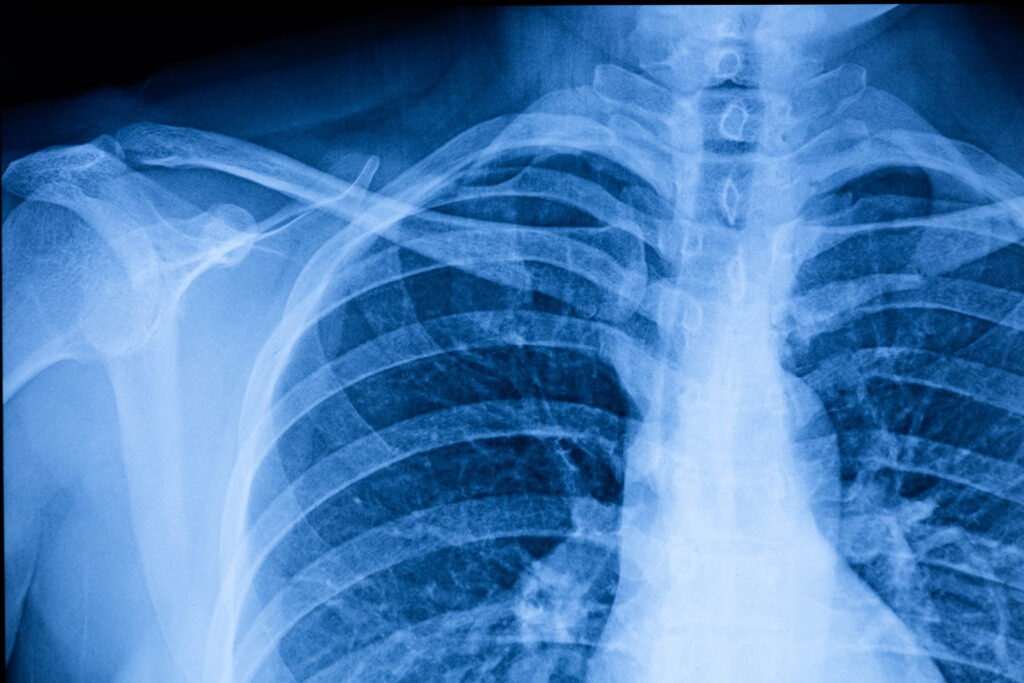

In-House Imaging: Fast Answers, Faster Care

Service Focus: X-Ray & Ultrasound

When you’re in pain or facing a health concern, waiting days for imaging results isn’t ideal. That’s why OSTEODOX offers on-site X-ray and ultrasound services—giving you faster answers, without the runaround.

Whether you’re dealing with a sprained ankle, joint pain, or abdominal discomfort, our in-house imaging allows our providers to evaluate your condition in real time and take immediate action.

Having everything under one roof doesn’t just save you time—it allows for more accurate, coordinated care from diagnosis to treatment.

Did You Know? Our imaging services are fully integrated with…